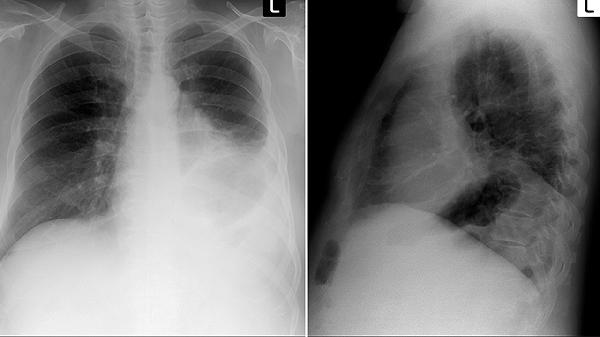

戒煙后6個月內(nèi)是肺部自潔的關(guān)鍵期,需保持環(huán)境濕度適宜,每日開窗通風(fēng)2次。出現(xiàn)持續(xù)咳嗽伴黃痰、胸痛等癥狀時及時就診,可能提示合并慢性支氣管炎或肺部感染。長期吸煙者建議每年進行低劑量螺旋CT篩查,早期發(fā)現(xiàn)肺氣腫等病變。